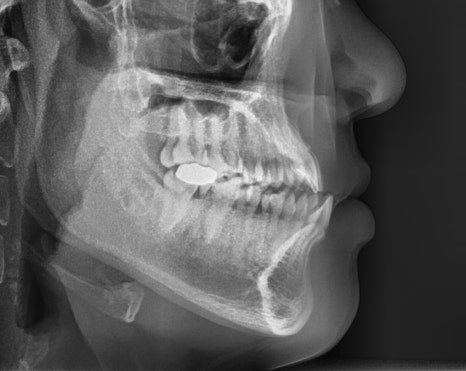

오늘 살펴볼 세라믹치과의

반대교합 치아교정전후 사례는

반대교합, 아래턱 돌출, 비발치 교정으로

진행한 증례입니다.

치료계획

🔎 교정시작 나이 : 24세

🔎 교정시작 이유 : 반대교합, 치아 벌어짐

🔎 교정 소요일 : 약 1년 2개월

앞니 반대교합

아래턱 돌출

치아 벌어짐

또한 치아배열도 좋지 않았고

비대칭이 함께 있는 상태였습니다.

-부정교합 개선을 위한 '비발치 교정'

(예상 기간 24개월)